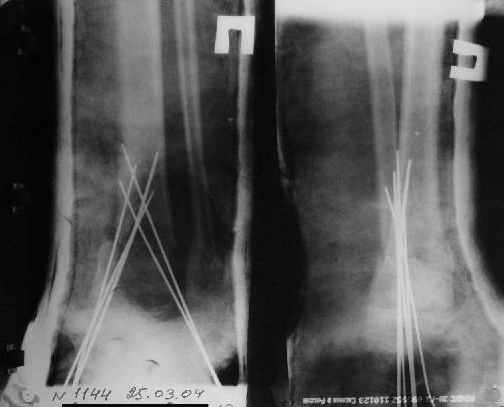

Ребенок 12 лет, поступил после падения с высоты примерно 2,5м.

Перелом костей н\3 правой голени со смещением. Перелом большеберцовой кости можно охарактеризовать как компрессионно-оскольчатый.

Скелетное вытяжение за пяточную кость.

Так как речь зашла непосредственно о травме, см этапные

снимки. Как все было

Первичные